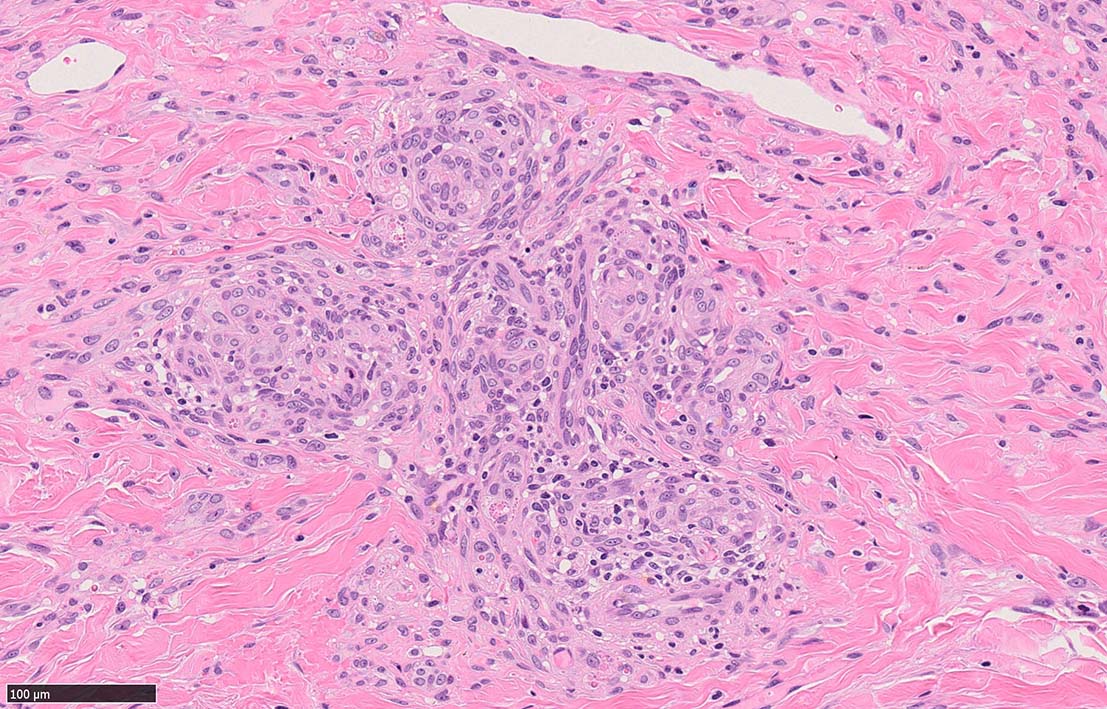

結節性病変の形成

紡錘形細胞が著しく増生し束状に走行する部分と, 内皮細胞様細胞による多数の小管腔構造が巣状にひろがり, 一見, 線維腫と血管腫が混在しているように見える. 一部の症例を除き, これらの増生細胞は異型性に乏しいことが多い.

細血管周囲に血管内皮様の紡錘形細胞が増生, 一部に赤血球をいれた裂隙の形成がある. 細胞の異型はみられず, mitosisの増多もない. hemosiderin-laden macrophageが散在する.

病変は真皮内に現局している. 初期斑状病変に相当すると考えられる. 本例では, 特徴とされる形質細胞浸潤増加はみられない.